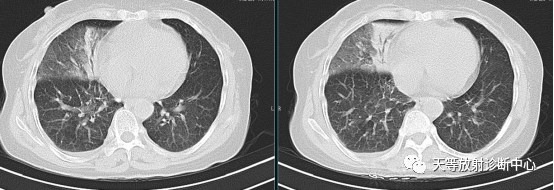

上图:左边病例:支原体肺炎,右侧肺炎,肺不张。

右边病例:两侧肺门影增大增浓。

病例来源:庄丽霞 张 芬.小儿肺炎支原体感染321例临床和影像学特点分析[J].福建医药杂志.2020.42(1):91-93.